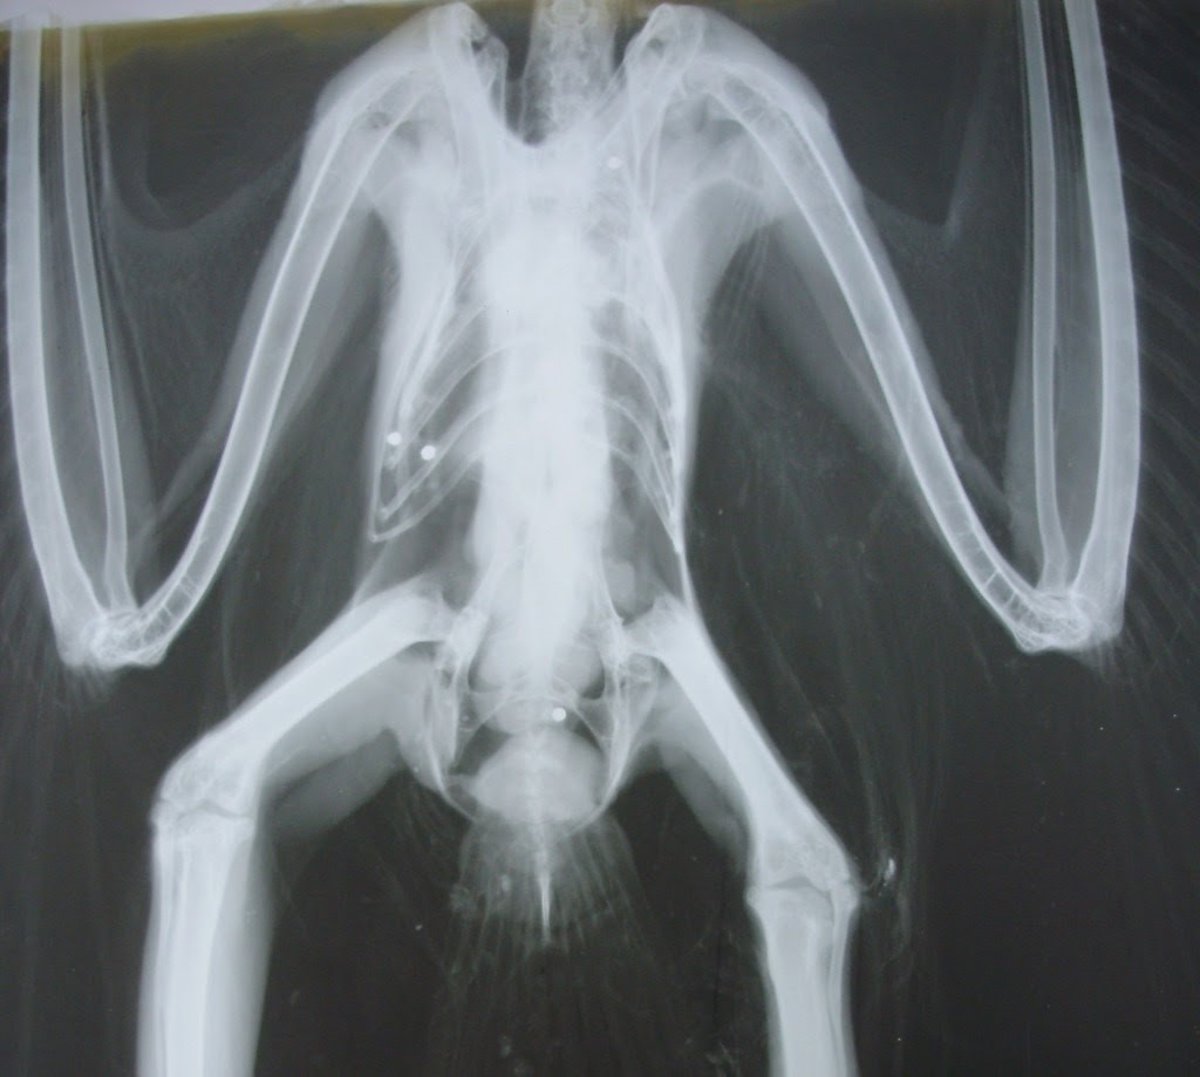

Archivo - Radiografía de un ave con perdigones de plomo

Archivo - Radiografía de un ave con perdigones de plomo - SEO/BIRDLIFE - Archivo

La ONG calcula que entre 4.000 y 5.000 toneladas de plomo se vierten a la naturaleza la UE cada año y que estos perdigones son ingeridos comúnmente por aves acuáticas como cisnes, flamencos, patos y gansos, que las confunden con las piedrecillas que utilizan para facilitar la digestión de las duras semillas que comen.

En la actualidad, la Agencia Europea de Sustancias y Mezclas Químicas estima que anualmente esto genera la muerte por plumbismo de más de un millón de aves acuáticas.